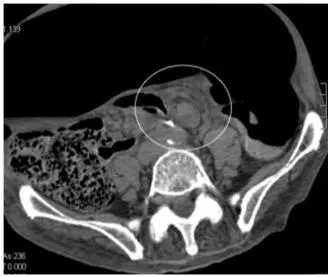

B1. Abdomen CT

Whirl pattern, caused by the dilated sigmoid colon around its mesocolon & vessels

Bird-beak appearance of the afferent and efferent colonic segments

Whirl sign

Bird beak sign